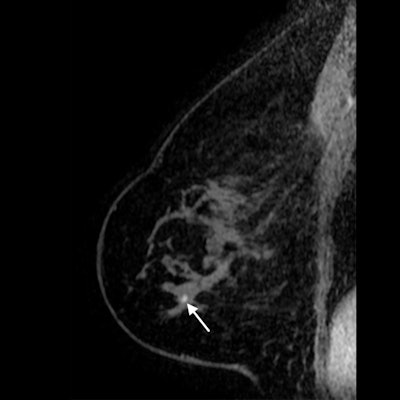

Sagittal T1-weighted fat-saturated contrast-enhanced MRI image of 71-year-old woman with history of breast cancer who presented for screening MRI. Arrow points to 4-mm focus in right breast at middle depth. MRI-guided core needle biopsy showed grade 1 invasive lobular carcinoma. All images courtesy of RSNA.

Screening mammography image of same patient taken six months prior. Right mediolateral oblique tomosynthesis image was interpreted as benign, with the circle highlighting postsurgical changes. The cancer diagnosed after MRI screening was confirmed to be an interval cancer.The findings led the authors to question the clinical relevance of DBT for women with a personal history of breast cancer. Although significant, the absolute reduction in the abnormal image interpretation rate was fairly small at 0.4%. Still, the higher specificity could be a benefit for women with prior cancer by reducing the number of women recommended for biopsy.